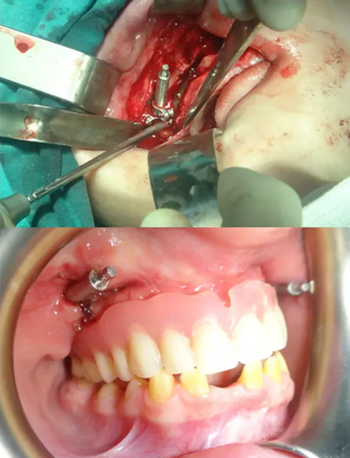

該患者的治療目標(biāo)是恢復(fù)牙頜面的正常功能和美觀,包括頜骨的垂直關(guān)系及咬合關(guān)系。治療步驟分別是術(shù)前診斷,制備引導(dǎo)性義齒,外科手術(shù)(Le FortⅠ型截骨牽張成骨),種植體植入及最終的義齒修復(fù)。上頜牽張 10 天(每天 0.5 mm×2 次),二期拆除牽張器并行種植體植入,術(shù)后出現(xiàn)輕微的感覺異常及開口困難,癥狀于 2 周后緩解。經(jīng)頭影測量可見 A 點(diǎn)、ANS 點(diǎn)、上唇、鼻尖點(diǎn)分別前移 6 mm、 8 mm、5 mm、2 mm。最后行義齒修復(fù)上頜牙列缺失?;颊邔?duì)最終的美觀及功能恢復(fù)感到滿意。